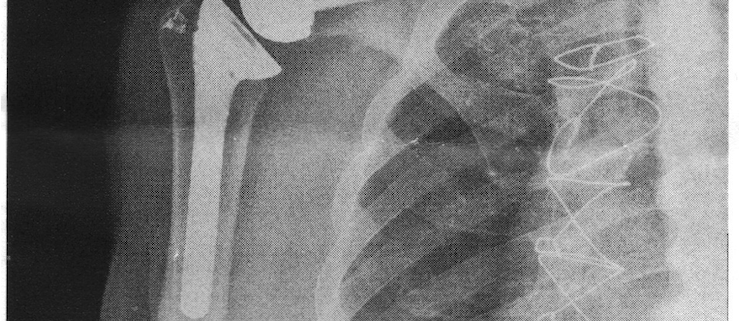

For the last two ski seasons my right shoulder has been giving me increased trouble when poling, especially in the flats. I visited my orthopedist, and x-rays revealed my shoulder had inoperable bone spurs. I needed a total shoulder joint replacement. This would be my 11th surgery in 20 years. Mentally, I wasn’t ready for another surgical procedure and stint at rehab. I inquired what my options were short of surgery. For the next two years I received quarterly cortisone shots in the shoulder. While effective over that period, last season the shots were no longer providing much pain relief, as predicted by my physician. It was time for the replacement surgery.

The new reverse joint replacement